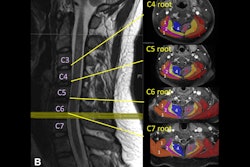

An MR image of a patient in their early 20s shows nerve injury of the left brachial plexus in the neck. The patient experienced left arm weakness and pain after recovering from COVID-19 respiratory illness, which prompted them to see their primary care physician. As a result of the MRI findings, the patient was referred to the COVID-19 neurology clinic for treatment. Image and caption courtesy of Northwestern University.Determining the cause makes treatment more effective, according to the team. If the cause is due to injury from prone positioning, a patient would be referred for rehabilitation or peripheral nerve surgery. If nerve damage has been caused by inflammatory response, the patient should see a neurologist. And if the damage is caused by hematoma, blood thinner medications should be adjusted and surgery may be necessary, according to the group.

Ultrahigh-resolution ultrasound and MR neurography (which visualizes the peripheral nerves) can localize the problem and assess the severity of nerve damage and whether that damage has affected the muscles, according to the team.

"Peripheral nerve imaging aids diagnosis and may guide management in COVID-19 patients with neuromuscular symptoms arising from the infectious disease, hospitalization course, or secondary to a complication in treatment," the group concluded.